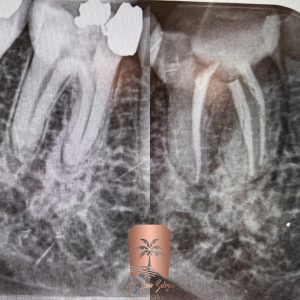

Diagnosis of dental problems

Correct diagnosis is the first step in nerve extraction treatment. Our dentists identify signs of infection and nerve damage by performing detailed examinations and modern radiographs. This allows us to choose a more optimal treatment method for each patient. Discipline and attention to the needs and conditions of each patient is one of the principles of our clinic.

Nerve removal process

After diagnosis, it is time to clean the root canals. This process involves removing damaged and infected tissue that can lead to pain and serious infections. Our specialists clean the canals using advanced and high-precision tools to prevent new infections. This step requires high skill and experience so that the patient experiences the least pain.